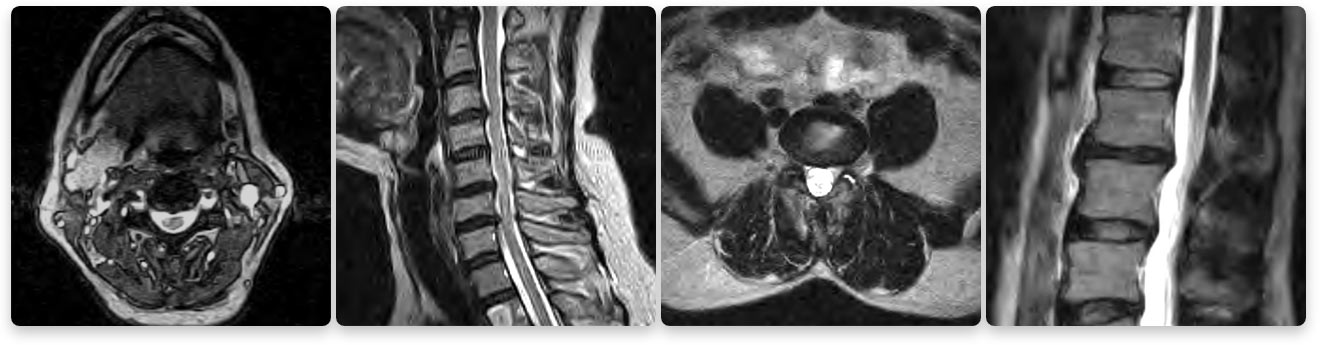

Texas Health Southlake's Imaging Department's 1.5T High Definition MRI Images

Seeing is believing. Do not compromise quality for a lower price. The images above compare a low strength machine to our 1.5T high-field machine. Two of the biggest factors that contribute to MRI image quality are strength of the magnet and skill of the technologist.

Beware of MRIs with lower magnet or tesla strength (Tesla is a measurement of magnetic field strength). The gold standard of MRI today is a 1.5T (T stands for tesla) strength MRI because it produces extremely clear images for a very accurate diagnosis. A lower-strength MRI produces images where the quality is much lower. You want to take care that you are not compromising your diagnosis when choosing an MRI.

1.5 tesla indicates the field-strength of the magnet used to obtain the images – the higher the field-strength, the more clear or detailed the images. A radiologist is looking to obtain the highest level of clarity for the most accurate diagnosis. Think of a spine injury. Let’s use, for example, a bulging disk. An MRI will show the anatomy of the vertebrae as well as the disks, spinal cord and the spaces between the vertebrae through which nerves pass. With such a complex image, your doctor will want the most clear, distinct picture so they can accurately assess the injury and make the proper diagnosis for treatment. The strength of the magnet is extremely important to achieve this clarity.

Lower strength means a less detailed image. The physician will have a harder time diagnosing the problem if he or she is looking at a low-quality image. These scans often take longer, making the patient more susceptible to movement resulting in reduced image quality. Lower image quality may lead to a longer wait time for the physician to read the scan or even misdiagnoses. Often prior to therapy, the entire scan may need to be redone. This costs you and your insurance company more money and may delay your diagnosis and treatment.